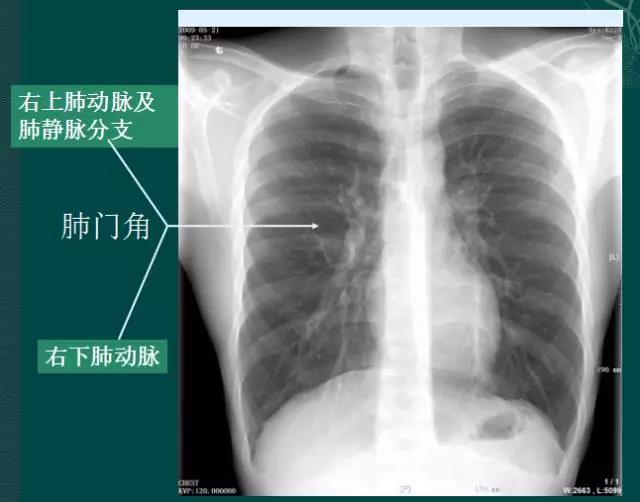

4.肺门的大小和位置

x线肺门指肺动脉、肺叶动脉、肺段动脉、伴行支气管以及肺静脉构成。

右肺门可分为上、下两部。上部约占1/3,由上肺静脉、上肺动脉及下肺动脉后回归支构成。上肺静脉下后干构成右上肺门的外缘;右肺门下部 约占2/3,由右下肺动脉干构成,其正常宽度不超过15mm,沿中间段支气管外缘平行向外下走行。右肺门上、下部相交形成一钝的夹角,称肺门角,正常该角顶清晰。如下图